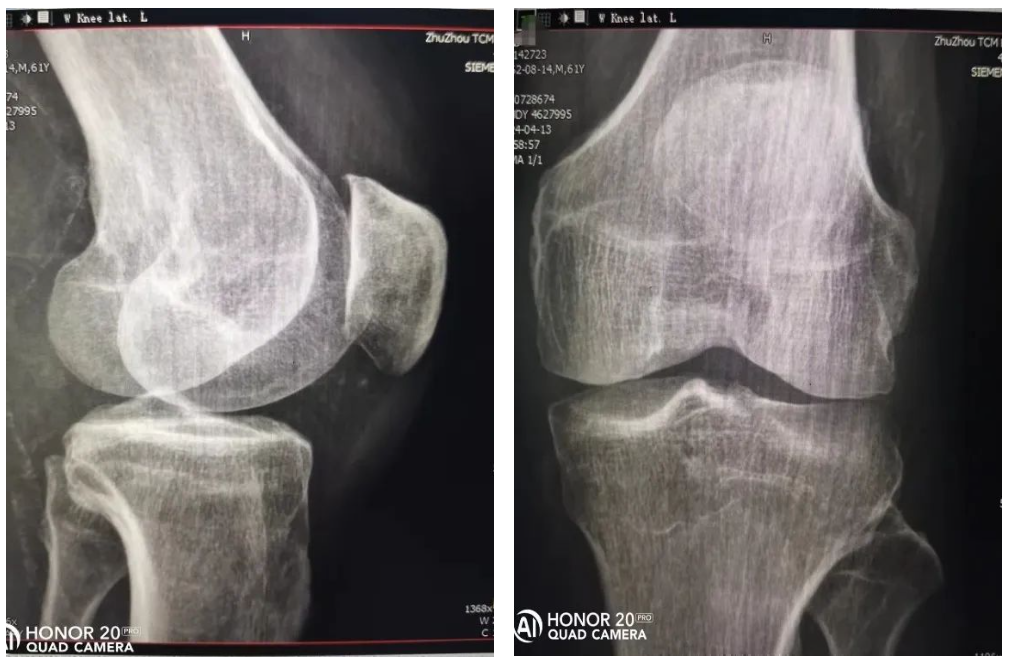

尿毒症维持血透的张师傅,一直都没有高尿酸血症,但最近遇到一个不小的麻烦,膝关节疼痛剧烈,并有肿胀、发热,不能正常行走,一度有放弃血透的念头。这一住院才发现得了晶体性关节炎。晶体性关节炎,顾名思义就是结晶体沉积在关节软骨及其周围组织所导致的关节局部炎症,严重时可导致发热、乏力、食欲减退等全身炎症表现,影响患者生活。

大家熟知的晶体性关节炎就是尿酸盐沉积在关节内所导致的痛风,其实结晶体除了尿酸盐结晶,还有焦磷酸盐结晶、碱性磷酸钙结晶(羟磷灰石)等。上述晶体性关节炎所导致的临床表现有诸多相似性,但鉴别诊断需要依据病程、既往病史、实验室和影像学检查以及受累关节作出初步判断,诊断金标准需要通过偏振光显微镜下检查关节液来进行确诊。在偏振光显微镜下,单尿酸钠晶体呈针状,具有很强的负双折射性。焦磷酸钙晶体呈多态性并显示出弱的正双折射。

尿毒症患者之所以容易出现晶体性关节炎,主要与甲状旁腺功能亢进,导致钙磷代谢失调,当钙磷浓度超过了羟磷灰石结晶溶解度,即促进结晶体的形成。另外,血液透析患者,血浆焦磷酸盐浓度下降,也促进了血管、关节软骨的钙化。